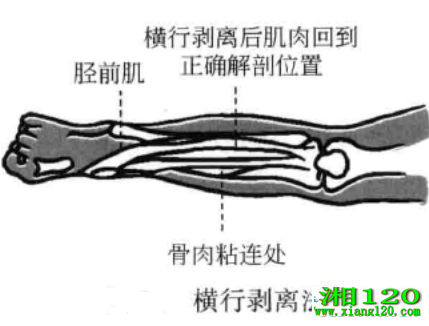

2、横行剥离法

当肌肉、韧带和骨发生粘连时,将刀口线沿肌肉或韧带走向平行剌入患处,当刀口接触到骨面时,做和肌肉或韧带走向垂直铲剥,将肌肉或韧带从骨面上铲起,感觉到针下有松动感时出针。